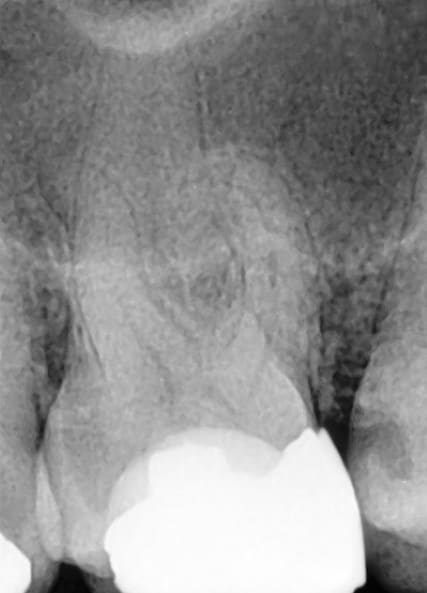

In narrow, curved, or partially calcified canals, progression may be limited. It is advisable not to force the instrument but to increase coronal flaring or establish a manual glide path to size 20 before reattempting apical progression. In most molar cases, however, the described glide path–free crown-down technique allows safe and effective shaping (Figure 4 and Figure 5).